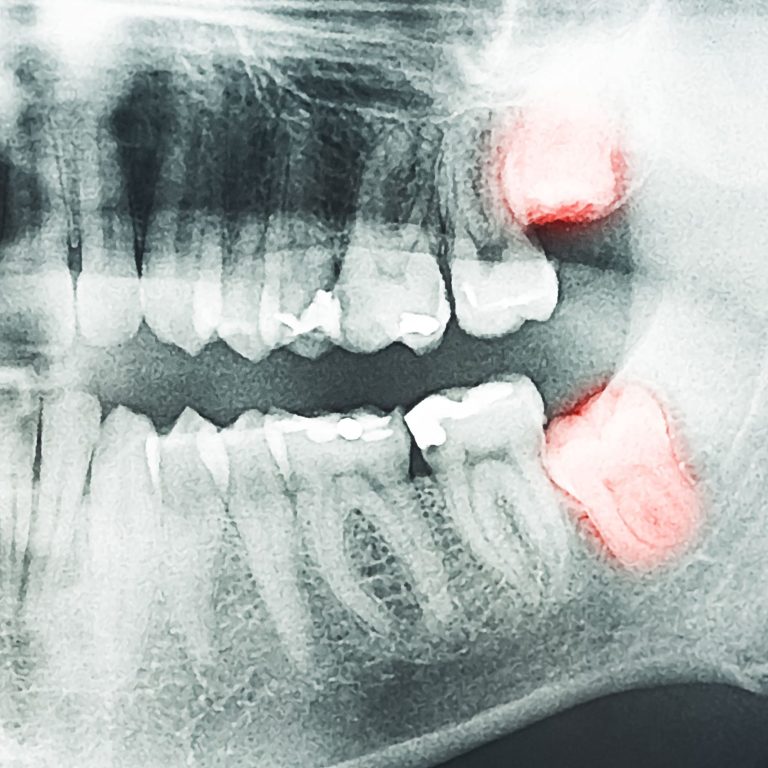

ExtractionsGentle and precise removal of troublesome wisdom teeth, providing relief from pain and preventing potential oral complications.by adminJanuary 19, 2024

Pompano Beach & Coral Springs Wisdom Teeth ExtractionsSwift and reliable dental care when you need it most, ensuring immediate relief and expert solutions for dental …by adminJanuary 19, 2024